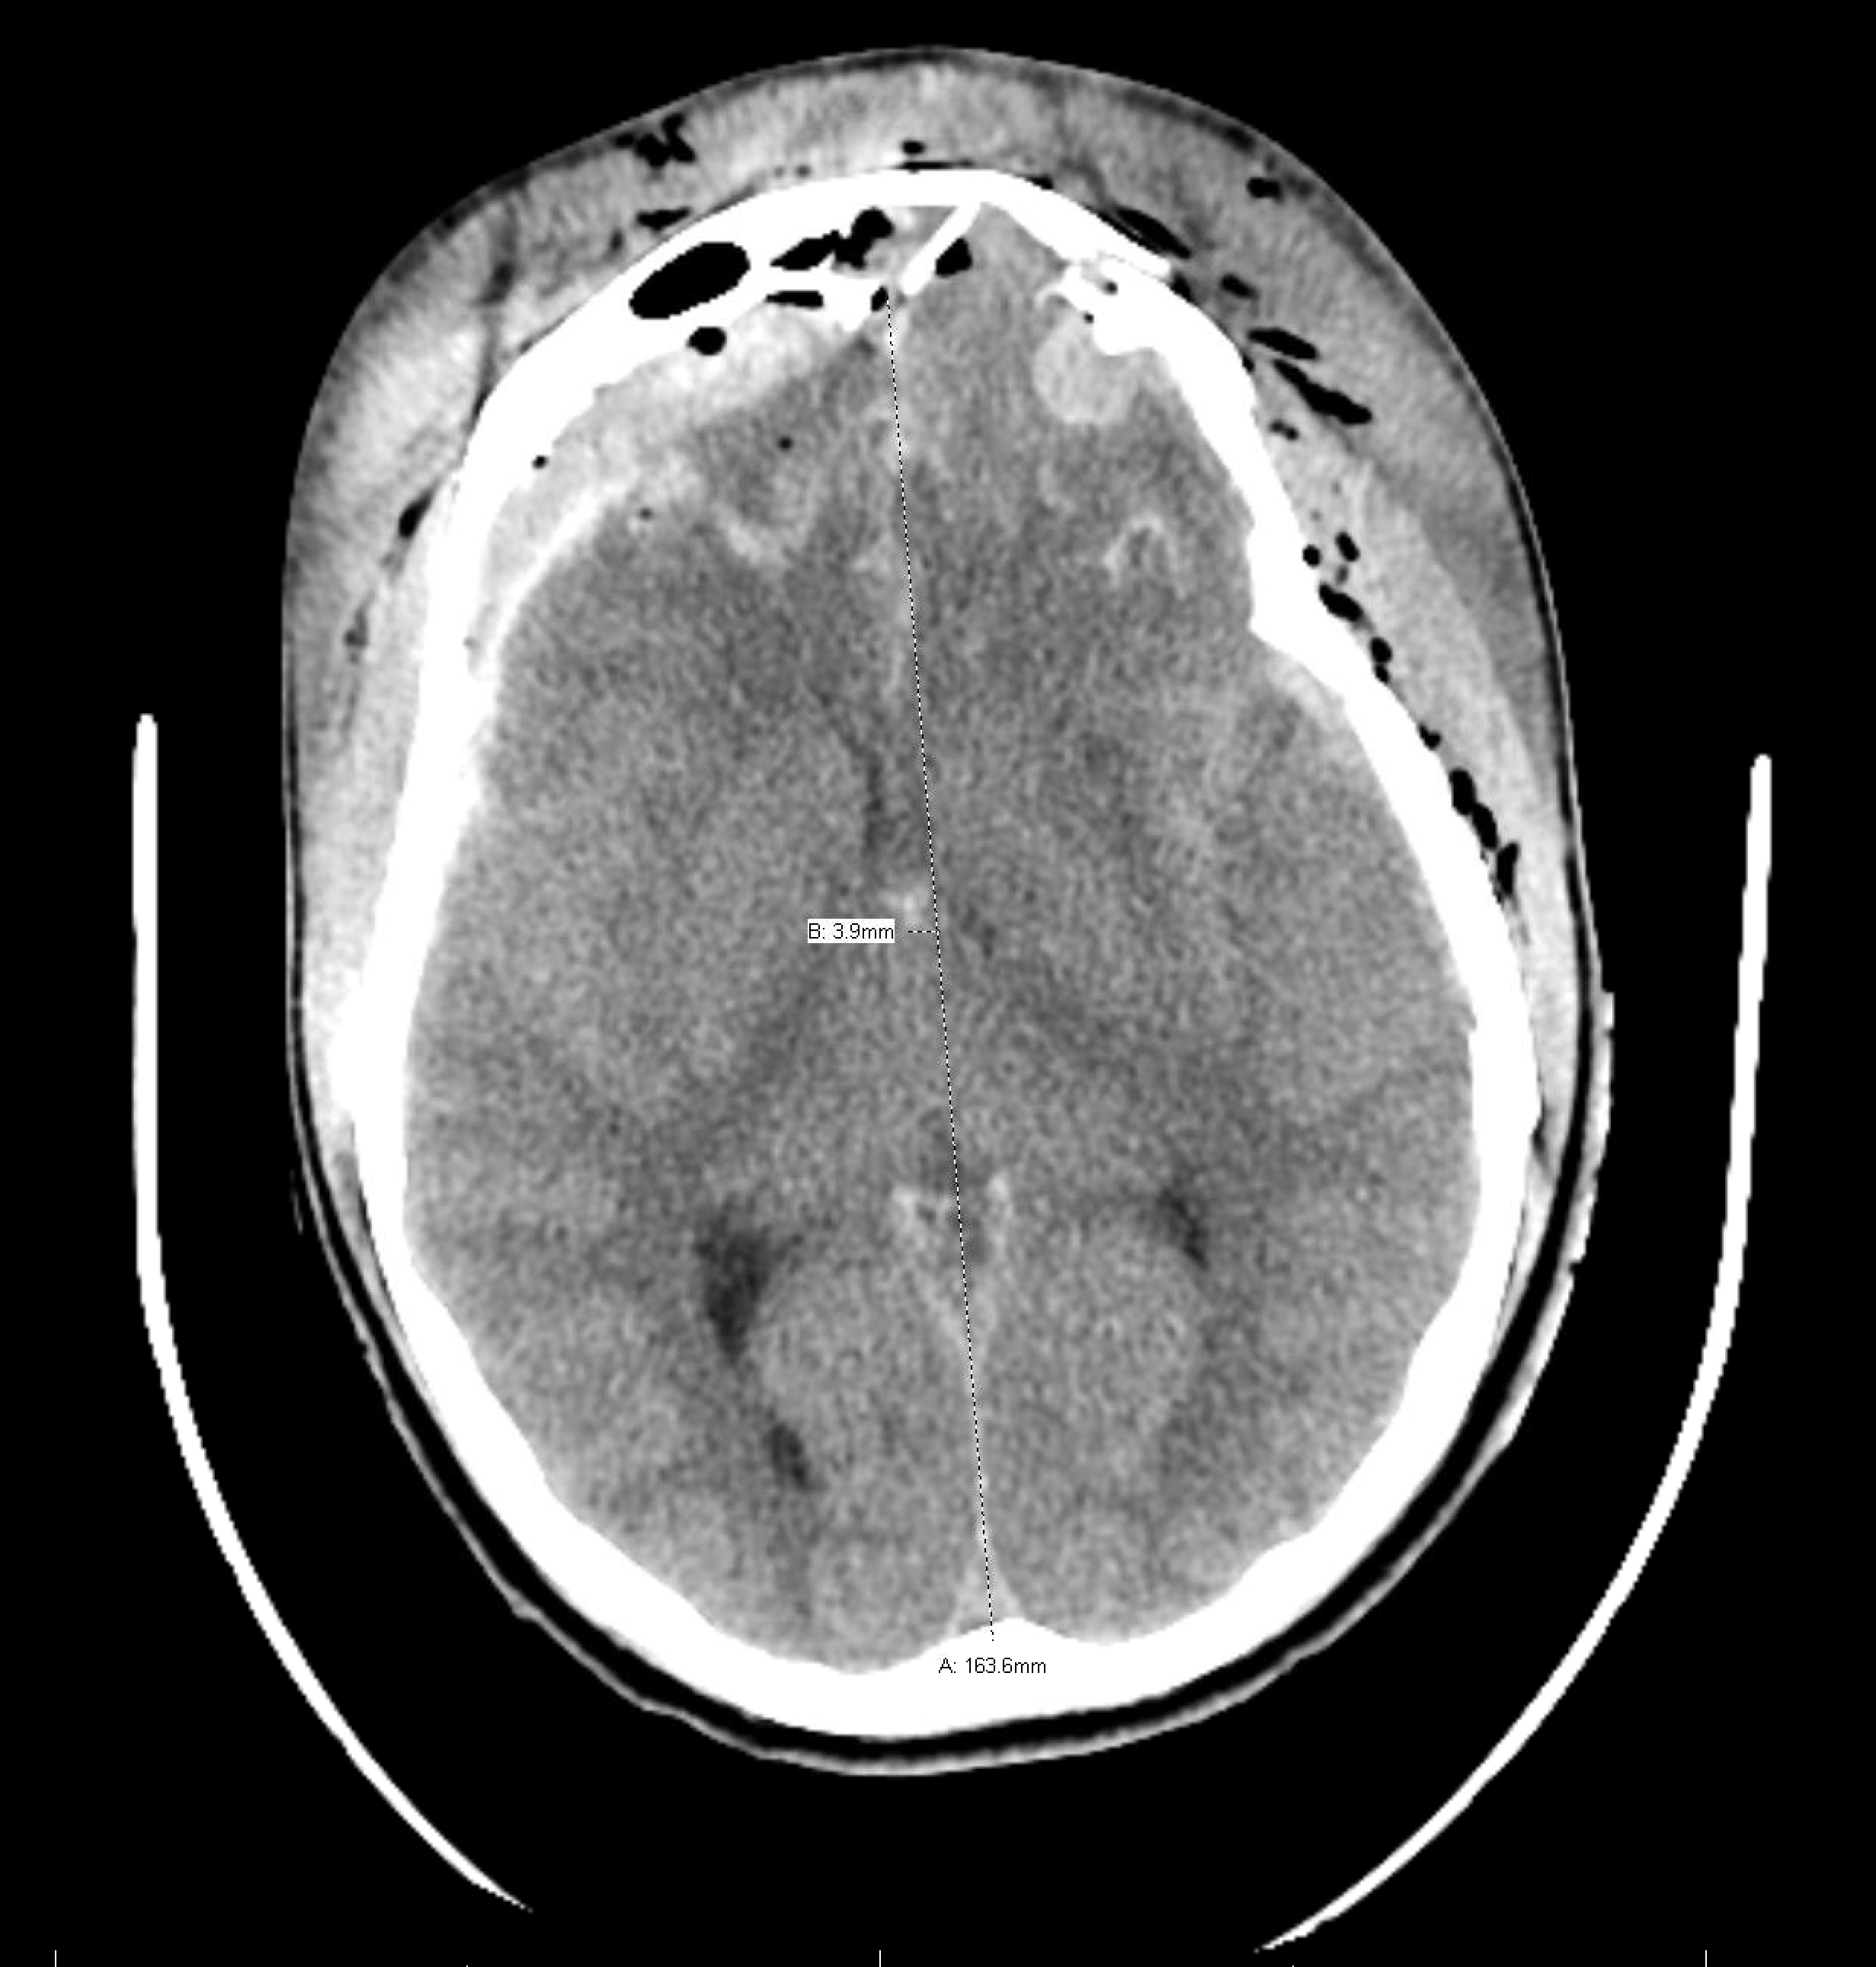

Age: 18

Sex: Male

Indication: Trauma

Sample ReportNo evidence of intracranial perfusion. While not diagnostic in itself, this finding would support a clinical diagnosis of brain death.